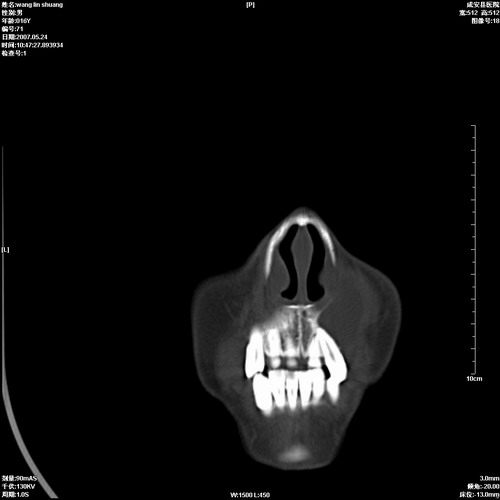

病人,男 16岁,鼻旁右肿胀,其余无不适感,ct图片

1、典型右侧根尖囊肿。

2、双侧上颌窦、筛窦、蝶窦炎

1\\左侧上颌骨含牙囊肿

2\\两上颌窦炎

右侧上颌骨含牙囊肿.双侧上颌窦炎症.

右侧上颌骨含牙囊肿.双侧上颌窦、蝶窦右侧炎症.

1、左侧上颌骨含牙囊肿。

本人同意根尖囊肿,双侧上颌窦、筛窦、蝶窦炎.

典型的右侧上颌骨含牙囊肿,双侧上颌窦、右侧蝶窦炎症。